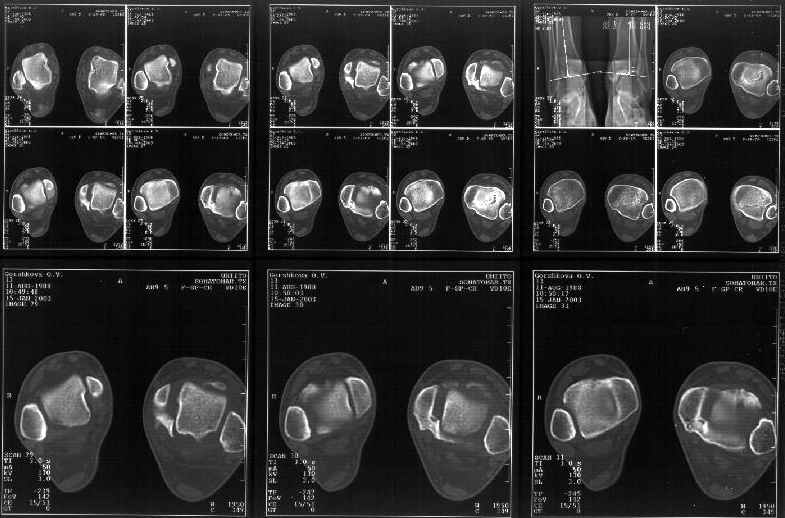

Мне в тоже время совершенно ясно видно по той же КТ, по 4 срезам, расположенным в центре и вверху пленки, что перелома внутренней лодыжки не было, в следующем собщении я приложу увеличенный фрагмент томограммы. А к этому письму прилагаю увеличеный фрагмент послеоперационной рентгенограммы, где выделил отколотый фрагмент

позади внутренней лодыжки. И он, как я вижу, находится между стержнем и тараном. А перелома внутренней лодыжки, и тем более смещения, IMHO

не определяется.

Отправитель: Alexander Chelnokov 12 Январь 2003, 14:55

Здесь 4 среза, начиная от основания лодыжки и проксимальнее. Где, по Вашему мнению, проходит линия перелома, отделяющая переднюю часть внутренней лодыжки от большеберцовой кости? Заранее спасибо.

Я пометил линию перелома черной линией.

К сожалению на последних присланных срезах КТ нет более низкого, через таран, среза, который был на прежнем майле. На XR я попытался показать

стержень внутри сустава и то как он раскрывает пространство между тараном и мед. малеолом.

Сегодня пациентке сделали сравнительную КТ. А ксиальные и Фронтальные срезы приложены. Ваше мнение?

Фронтальные

Аксиальные

На КТ я попытался изобразить скромными своими способностями (А)- место перелома, (С)- нормальный суставной зазор меж тараном и тремя его маллеолами. (В)- образовавшийся в результате перелома широкий раза в три зазор, позволяющий, по-моему, сублюксацию тарана при ходьбе. В свете данных КТ, критически важных, я бы предложил вертикальную остеотомию места перелома

задне-внутренним подходом и фиксацию мед. маллеола прижатым к тарану с помощью тонкого compression screw. После этого гипсовый сапожок и немедленное расхаживание ноги.